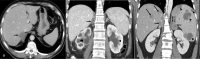

The purpose is to discuss abdominal tuberculosis mimicking malignancy involving the abdominal viscera. TB of the abdominal viscera is common, especially in countries where tuberculosis is endemic and in pockets of non-endemic countries. Diagnosis is challenging as clinical presentations are often non-specific. Tissue sampling may be necessary for definitive diagnosis. Awareness of the early and late disease imaging appearances of abdominal tuberculosis involving the viscera that can mimic malignancy can aid detecting TB, providing a differential diagnosis, assessing extent of spread, guiding biopsy, and evaluating response.